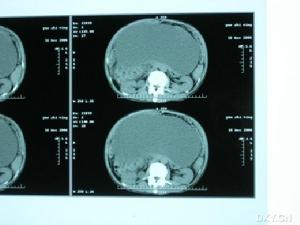

(3)CT掃描:可提供最佳的囊腫影像診斷,可提供確定位置、並可定性,有利於腸系膜囊腫的鑑別診斷。